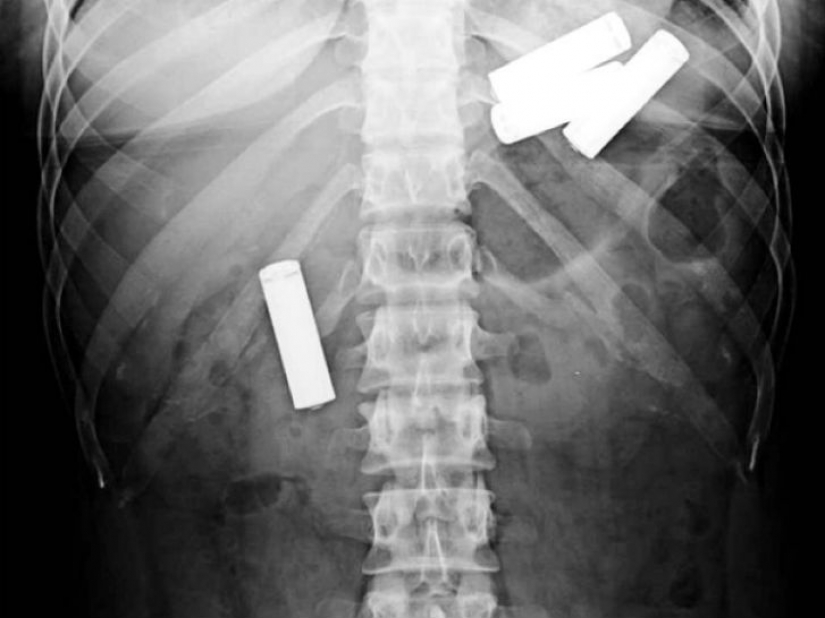

Here the batteries, perhaps theyíre only children. X-ray 13-month-old baby.